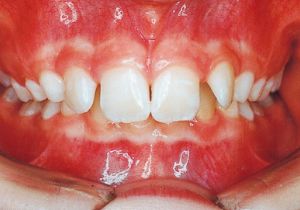

Age at Initial Visit: 11years 3month, Male / Deep bite. Protruding upper bite, Spaced arch.

2 After Treatment 6-24-’95

Class II deep bite in mixed dentition. A significantly large overjet and a spaced arch are observed. The cephalometric X-ray shows that the anteroposterior displacement of the maxilla and mandible is not particularly large (ANB 5°), but the nasal floor is elevated anteriorly, providing evidence supporting a history of thumb sucking. The skeletal form shows a relatively slight mandibular body deficiency, but the mandibular ramus is adequately sized and appears likely to develop sufficiently. The use of headgear was planned to suppress maxillary anterior growth and achieve relative mandibular advancement. Treatment was performed without extraction, assuming continuity until the permanent dentition stage.